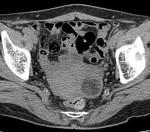

[画像診断]子宮筋腫変異型およびlipoleiomyomaについて 2010-07-07

[詳細は「タカ派の画像診断医」へ)